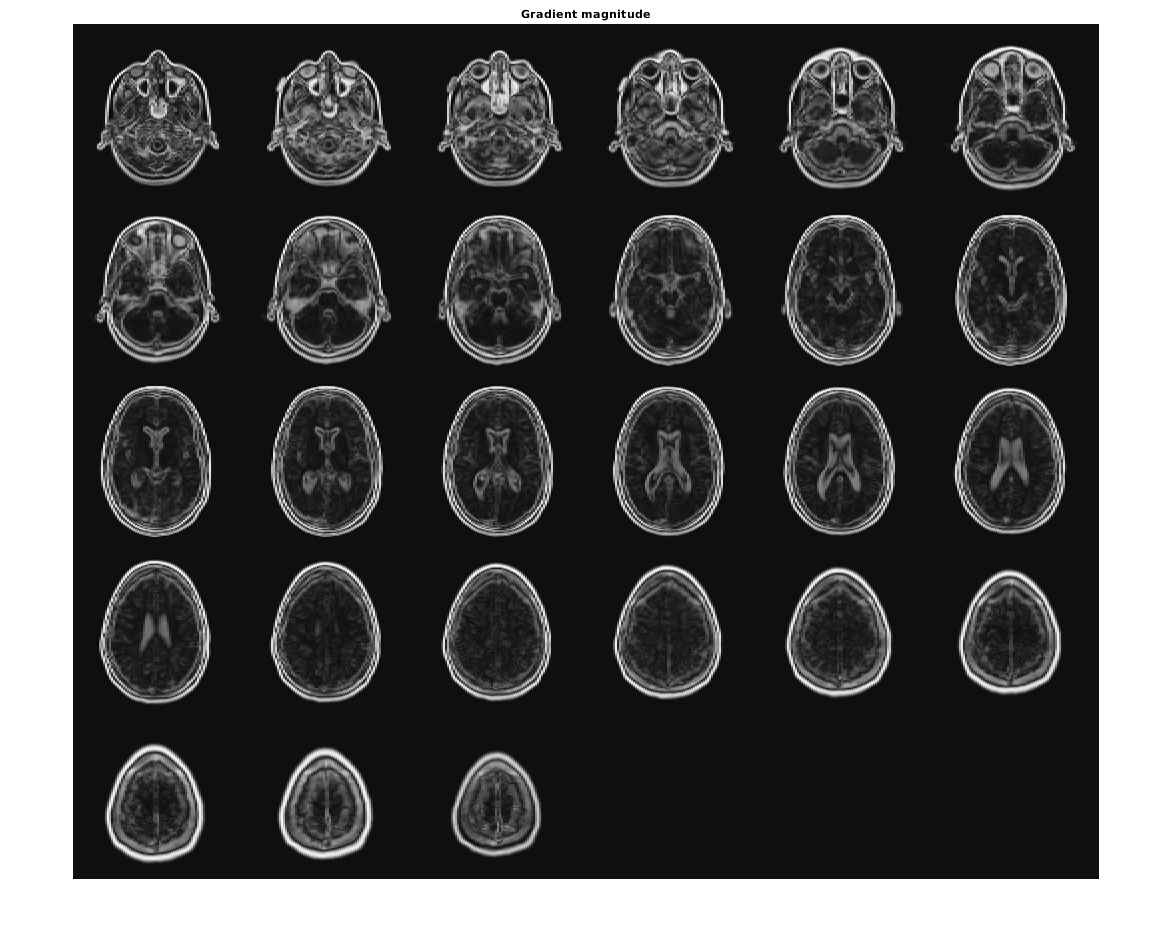

Визуализируйте величину градиента как монтаж.

figure,

montage(reshape(Gmag,sz(1),sz(2),1,sz(3)),'DisplayRange',[])

title('Gradient magnitude')